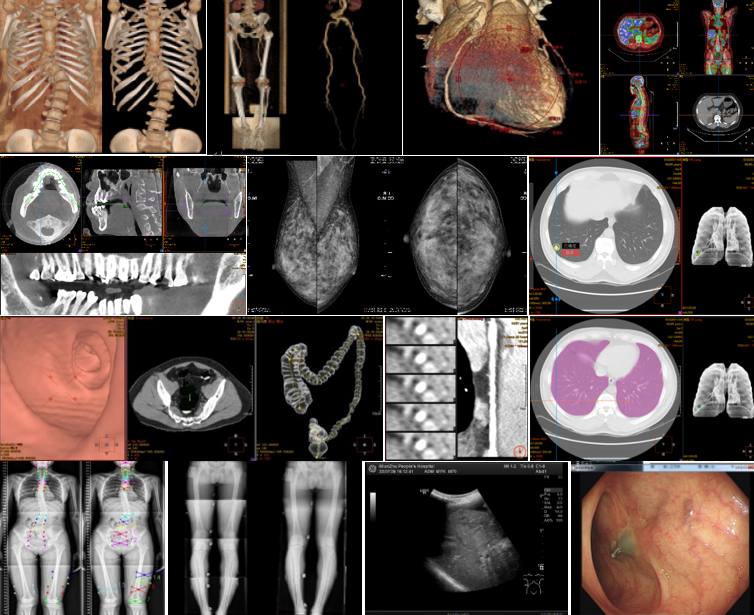

遵循化繁为简的设计原则,采用统一的工作空间,集成了丰富的临床工具集和高级功能。

支持放射、超声、内镜、核医学、介入、病理、心电等设备接入,使用同一个数据中心,方便数据共享和联合诊断。同时院内业务可以无缝扩展到区域,实现远程诊断。

强大的图像调阅与处理能力,支持显卡GPU运算,丰富的临床工具集

5、丰富的高级后处理工具集,支持一键去床、去骨、心血管重建、齿科重建、骨科测量、DR拼接、钼靶挂片等高级功能

7、支持DICOM超声和内镜